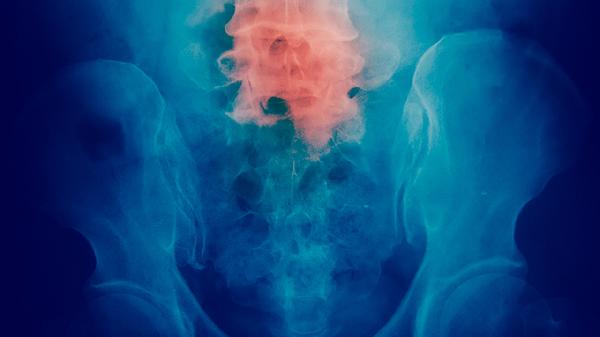

免疫治疗通过激活自身免疫系统对抗肿瘤,如帕博利珠单抗注射液阻断PD-1通路。适用于PD-L1高表达或微卫星不稳定的患者,可能引发免疫相关性肺炎等不良反应。治疗期间需密切监测甲状腺功能和肺部情况。